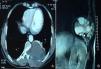

Hydatidosis is a parasitic disease caused by the larval form of Echinococcus granulosus. Thoracic and costo-vertebral hydatid cysts are very rare, accounting for 0.18%–1.21% of all cases.1 We report a thoracic and costo-vertebral multivesicular hydatid cyst in a 28-year-old man (Fig. 1A and B). The patient was treated by radical surgery via a posterior approach and anti-parasitic medical treatment for a period of 6 months, and progressed well. Due to the location, number of affected vertebrae and degree of spinal cord compression, surgery can be high-risk. Thoracic spine and rib resection extending to the muscles and vertebrae, with the possibility of reconstruction or fixation and removal of cysts located in pulmonary or mediastinal sites can be achieved with posterior thoracotomy.2

(A) Chest computed tomography showing a left multivesicular hydatid cyst in the costo-vertebral area involving the 8th and 9th ribs and the corresponding D11–D12 vertebrae, with costal lysis and spinal extension and no signs of medullar compression. (B) Hydatid cyst on chest T2-weighted coronal magnetic resonance imaging showing solid matrix with numerous daughter cysts in the mass.